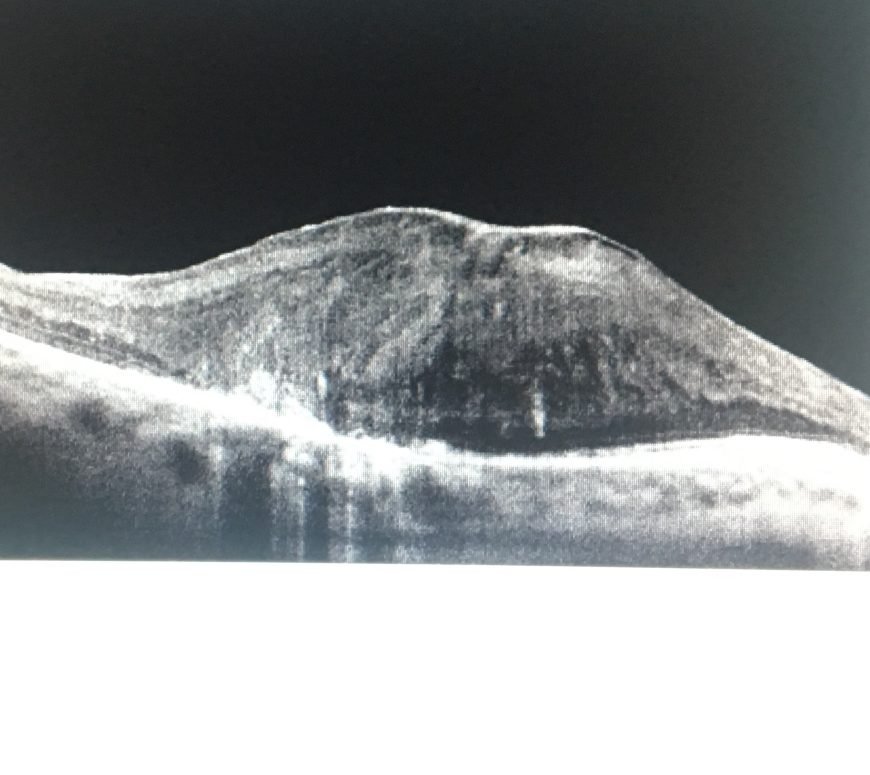

Il Dr. Elia Lo Schiavo, oculista, esegue una valutazione completa delle Malattie della Macula o Maculopatia napoli attraverso esami diagnostici avanzati come OCT (tomografia a coerenza ottica), fluorangiografia e test della visione centrale.